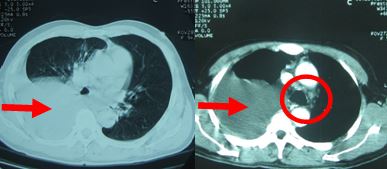

1. Chụp cắt lớp vi tính lồng ngực: Hình ảnh tràn dịch màng phổi phải, hạch trung thất (hình 1a)

Hình 1a: Hình ảnh chụp cắt lớp vi tính lồng ngực thấy tràn dịch khoang màng phổi phải (đầu mũi tên đỏ), khó đánh giá hạch trung thất (trong vòng tròn đỏ).

Hình 1b: Trên hình ảnh PET/CT sau 1 tháng điều trị thấy hạch trung thất kích thước 0,9 cm, max SUV=2,8 (đầu mũi tên đỏ), do bệnh nhân không chụp PET/CT trước điều trị nên khó đánh giá hạch trung thất mới xuất hiện sau điều trị hay hạch nhỏ đi sau điều trị, giả thiết hạch nhỏ đi sau điều trị phù hợp hơn do trên phim chụp CT ngực 64 dãy sau 5 tháng điều trị (xem hình số 10) không còn thấy hạch trung thất.

Trước điều trị: Tràn dịch màng phổi phải (mũi tên đỏ).                Sau điều trị: không thấy tràn dịch màng phổi phải

Sau 1 tháng điều trị: còn hạch rốn phổi phải,kích thước: 0,9 cm (vòng tròn vàng)

Sau 5 tháng điều trị: không còn hạch rốn phổi